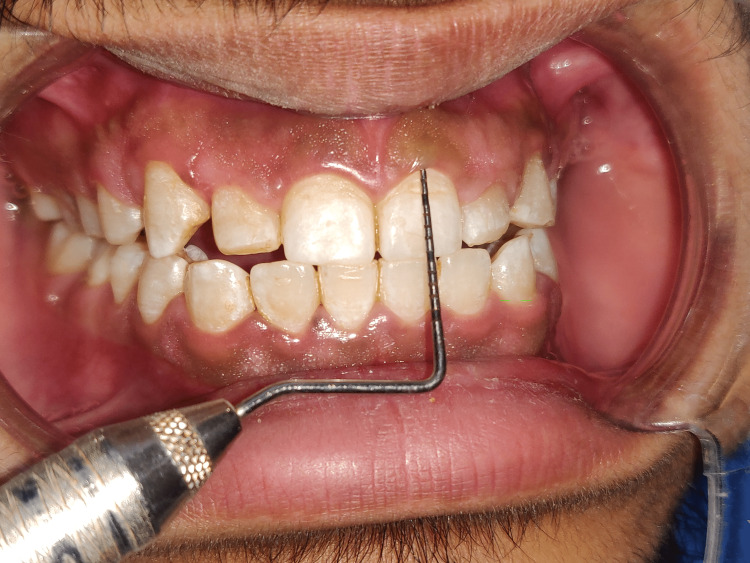

Short clinical crowns measured on the mid-buccal aspect of the height from the gingival margin to the incisal edge were found during the clinical examination to have healthy gingiva and periodontium (right central incisor - 8mm, right lateral incisors - 6mm, right canine - 7mm, left central incisor - 7mm, left lateral incisor - 5mm, left canine - 7mm) as depicted in Figures 3-8. As a result, the diagnosis of gummy grins due to altered passive eruption (type I - subgroup B) [9] was made, and it was determined to treat choice with aesthetic crown lengthening surgery with osseous reduction.

Figure 3. Clinical crown measurement of right central incisor as 8mm (11).

Figure 4. Clinical crown measurement of right lateral incisor as 6mm (12).

Figure 5. Clinical crown measurement of right canine as 7mm (13).

Figure 6. Clinical crown measurement of left central incisor as 7mm (21).

Figure 7. Clinical crown measurement of left lateral incisor as 5mm (22).

Figure 8. Marking depicting bleeding spots after pockets.